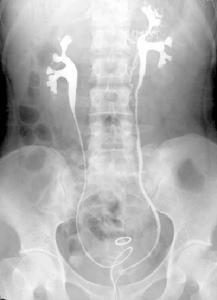

子宫输卵管造影是一种了解输卵管是否通畅、阻塞部位及宫腔形态的方法。 首先经过阴道将造影剂注射到子宫腔及输卵管内,然后进行 X光拍摄,或

简介:子宫输卵管造影是什么?子宫输卵管造影,指的是通过导管向子宫腔及输卵管注入造影剂,在X线下透视及摄片,根据造

输卵管造影经X线的子宫输卵管造影是通过导管向宫腔及输卵管注入造影剂,利用X线诊断仪行X线透视及摄片,根据造影剂在输卵管及盆腔内的显影情况来了解输卵管是否通畅、阻塞部位及宫腔形态的一种检查方法。 该检查损伤小,在有经验的医验操作下并附以数字X光机的应用能对输卵管堵塞作出正确诊断,准确率达98%,且具有一定的治疗作用,是目前用来了解输卵管是否通畅及通畅的程度和具体堵塞部位的最常用的检查方法。 【子宫输卵管造影技术】 (一)适应证 1、不孕症经丈夫精液检查无异常,病人BBT为双相且黄体功能良好已连续3个月经周期,仍未能受孕者。 2、曾有下腹部手术史如阑尾切除术、剖宫手术;曾有盆腔炎史如淋菌感染、产褥感染。 3、曾有慢性阑尾炎或腹膜炎史,现患子宫内膜异位症等,因不育而诊治,怀疑有输卵管阻塞者。 4、观察子宫腔形态,确定有无子宫畸形及其类型,有无子宫腔粘连、子宫粘膜下肌瘤、子宫内膜息肉及异物等。 5、腹腔镜检查有输卵管腔外粘连,拟作输卵管整形手术时的术前检查,因HSG能进一步提供输卵管腔内情况。 6、多次中孕期自然流产史怀疑有子宫颈内口闭锁不全者,于非孕时观察子宫颈内口有无松弛。 【